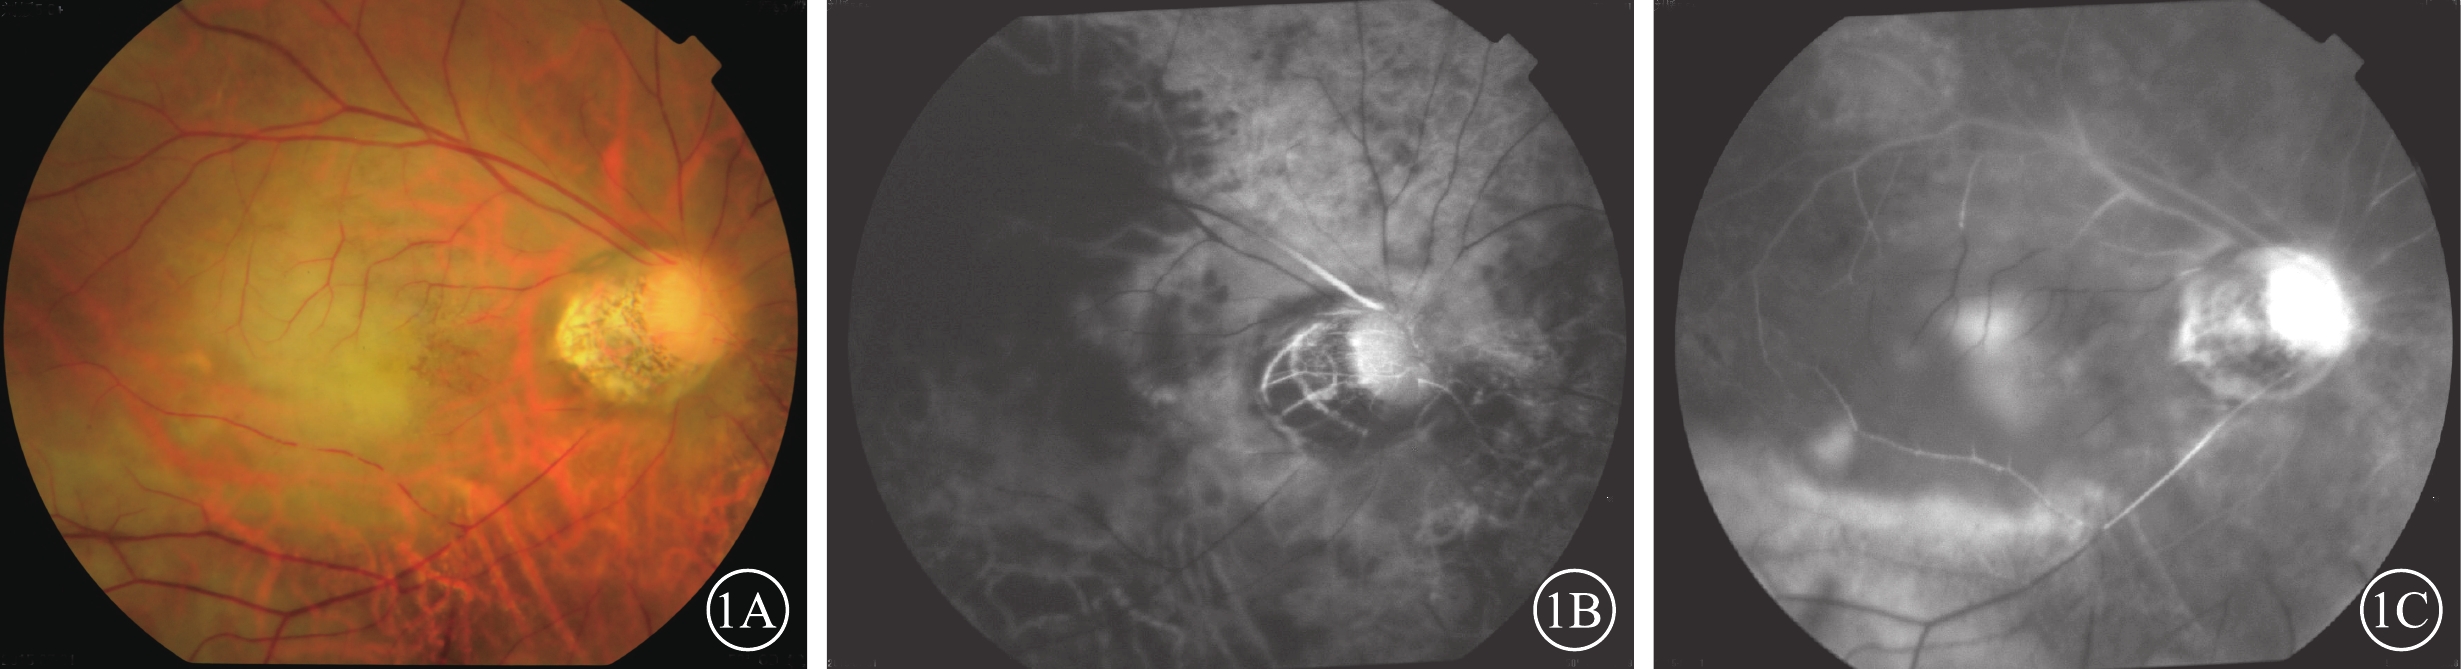

圖1

患眼彩色眼底、FFA像。1A示彩色眼底像,后極部灰白色水腫,黃斑櫻桃紅消失;1B、1C分別示FFA像。1B示臂-視網膜循環時間16.9 s;1C示主干-分支充盈時間11 min 5 s

圖1

患眼彩色眼底、FFA像。1A示彩色眼底像,后極部灰白色水腫,黃斑櫻桃紅消失;1B、1C分別示FFA像。1B示臂-視網膜循環時間16.9 s;1C示主干-分支充盈時間11 min 5 s

患眼視力無光感~0.6。20只眼中,單純OAO 3只眼(15%);OAO合并CAO 4只眼(20%)、MAO 1只眼(5%);單純RAO 7只眼(35%),其中CRAO(圖1)、HRAO、BRAO分別為4、1、2只眼;CRAO伴PCAO 1只眼(5%);PCAO伴NAION 1只眼(5%);CRAO合并DNAO 2只眼(10%);CRAO、PCAO合并右大腦中動脈阻塞1只眼(5%)(表2)。20例中,眼球運動障礙和眼瞼皮膚發紺4例(20%);合并面部疼痛、鼻部皮膚缺血壞死2例(10%)。顱腦CT檢查示右側大腦中動脈供血區域低密度缺血灶1例(20%)。MRA檢查發現顱內新發缺血灶6例(30%)。6例患者中,玻尿酸注射者5例,均為無癥狀的小血管阻塞。自體脂肪注射者1例,男,27歲。右眼視力無光感,眼球運動障礙;左側肢體偏癱。眼底可見后極部灰白色水腫,黃斑中心凹反光消失(圖2A);顱腦CT檢查,右側顳葉低密度梗死灶(圖2B);MRA檢查,右側眼動脈未顯影,大腦中動脈M2段閉塞(圖2C)。

患眼彩色眼底、FFA像。1A示彩色眼底像,后極部灰白色水腫,黃斑櫻桃紅消失;1B、1C分別示FFA像。1B示臂-視網膜循環時間16.9 s;1C示主干-分支充盈時間11 min 5 s

圖1

患眼彩色眼底、FFA像。1A示彩色眼底像,后極部灰白色水腫,黃斑櫻桃紅消失;1B、1C分別示FFA像。1B示臂-視網膜循環時間16.9 s;1C示主干-分支充盈時間11 min 5 s